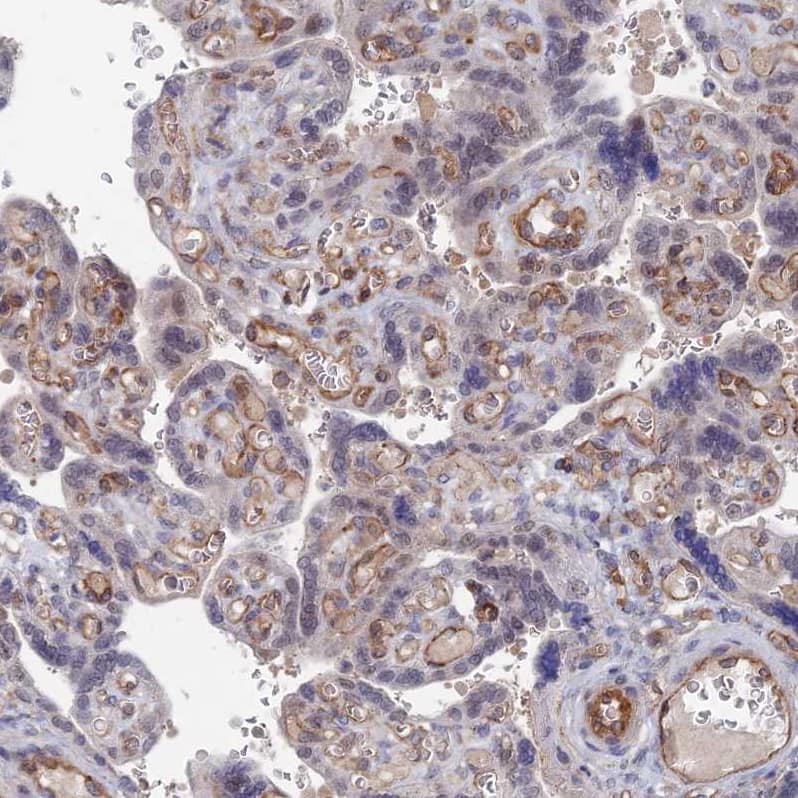

Staining of human placenta shows moderate membranous-cytoplasmic positivity in endothelial cells.